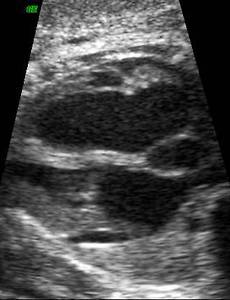

ebstein anomaly Tricuspid valveApical displacement of the septal leaflet. This is probably the most reliable diagnostic sign.Posterior leaflet usually displaced apically but the degree of displacement is variable.Anterior leaflet is not displaced and may be normal or large and redundant ("snail-like appearance").Small mobile parts of the leaflets lie deep in the RV.The above changes result in atrialization of t.. 2020. 3. 19. 이전 1 다음